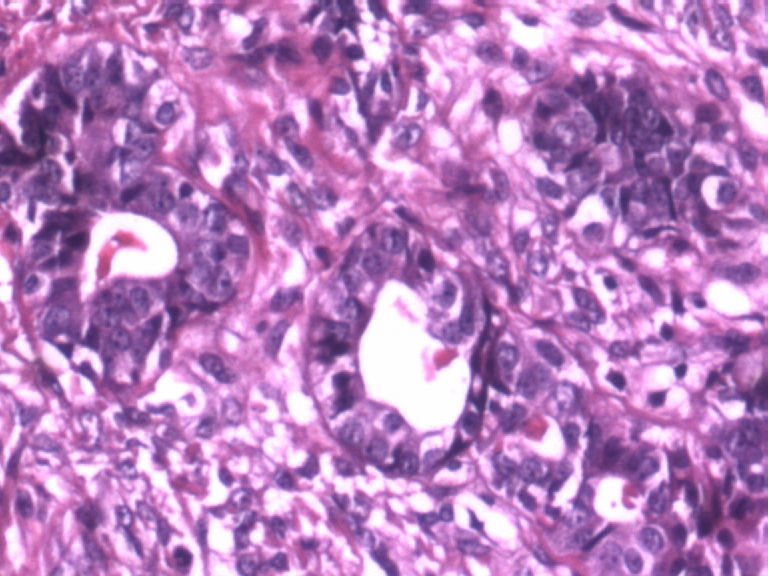

• 乳腺肿物图2

图2

患者,女,29岁,右侧乳腺肿物一个月。切面淡黄,均匀一致,质中。

标签:乳腺管状腺瘤

病变组织小叶结构未见,见管状、盲管状的腺管,周围似有空亮的肌上皮,腺上皮可见细小的核仁,染色质均细,导管上皮普通型增生。有包膜为盲管状腺瘤,则为腺病。

无则为腺病

肌上皮可见,导管不规则,细胞有异性,极性还可。有核仁,考虑乳腺腺病,部分腺体呈不典型增生。